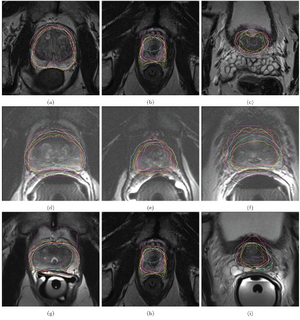

Publication: Proc Natl Acad Sci U S A. 2015 Nov 17;112(46):E6265-73. PMID: 26578786 | PDF Authors: Fehr D, Veeraraghavan H, Wibmer A, Gondo T, Matsumoto K, Vargas HA, Sala E, Hricak H, Deasy JO. Institution: Department of Medical Physics, Memorial Sloan Kettering Cancer Center, New York, NY, USA. Background/Purpose: Noninvasive, radiological image-based detection and stratification of Gleason patterns can impact clinical outcomes, treatment selection, and the determination of disease status at diagnosis without subjecting patients to surgical biopsies. We present machine learning-based automatic classification of prostate cancer aggressiveness by combining apparent diffusion coefficient (ADC) and T2-weighted (T2-w) MRI-based texture features. Our approach achieved reasonably accurate classification of Gleason scores (GS) [Formula: see text] vs. [Formula: see text] and [Formula: see text] vs. [Formula: see text] despite the presence of highly unbalanced samples by using two different sample augmentation techniques followed by feature selection-based classification. Our method distinguished between GS [Formula: see text] and [Formula: see text] cancers with 93% accuracy for cancers occurring in both peripheral (PZ) and transition (TZ) zones and 92% for cancers occurring in the PZ alone. Our approach distinguished the GS [Formula: see text] from GS [Formula: see text] with 92% accuracy for cancers occurring in both the PZ and TZ and with 93% for cancers occurring in the PZ alone. In comparison, a classifier using only the ADC mean achieved a top accuracy of 58% for distinguishing GS [Formula: see text] vs. GS [Formula: see text] for cancers occurring in PZ and TZ and 63% for cancers occurring in PZ alone. The same classifier achieved an accuracy of 59% for distinguishing GS [Formula: see text] from GS [Formula: see text] occurring in the PZ and TZ and 60% for cancers occurring in PZ alone. Separate analysis of the cancers occurring in TZ alone was not performed owing to the limited number of samples. Our results suggest that texture features derived from ADC and T2-w MRI together with sample augmentation can help to obtain reasonably accurate classification of Gleason patterns. Funding:

|

Example of (A) a GS 6(3+3) tumor and (B) a GS 9(4+5) tumor. The top row shows the ADC image with the computed energy and entropy values overlaid on the tumor. The bottom row shows the T2-w MR image with the computed energy and entropy values overlaid on the same tumor on the corresponding slice. The texture features were computed per voxel by using a 5×5×5 patch centered at each voxel. Tumors and normal structures were identified and volumetrically segmented on both the T2-w and ADC MR images using 3D Slicer. |